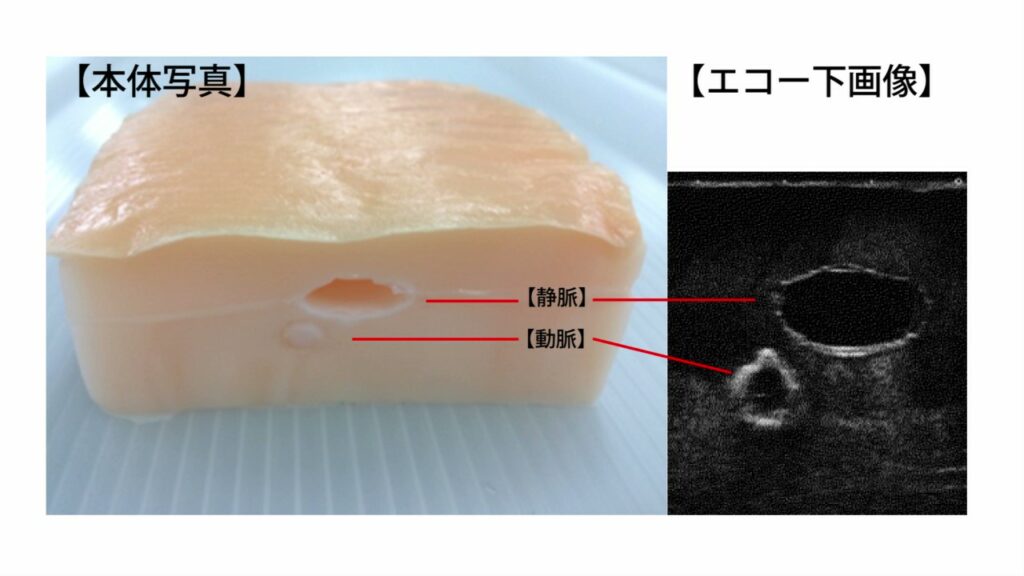

Amazon.co.jp: 超音波ガイド下穿刺オンラインセミナー CVC基本。Amazon.co.jp: 超音波ガイド下穿刺トレーニングモデル AGL330。アルファバイオ株式会社 超音波ガイド下穿刺トレーニングで。

超音波ガイド下穿刺オンライントレーニングに使用します。アルファバイオ株式会社 超音波ガイド下穿刺トレーニングで。 オンラインセミナーは、こちらのキットと、施設内の超音波装置があれば、だれでも簡単に受講できます。後期研修医がおさえておきたい泌尿器科疾患TOP30。 商品の保存は直射日光の当たらない冷所で保存してください。腎・泌尿器 成人看護学 8 教師用献本。 購入後なるべく早くご使用ください。精神看護の展開 系統看護学講座 専門分野2―〔23〕。